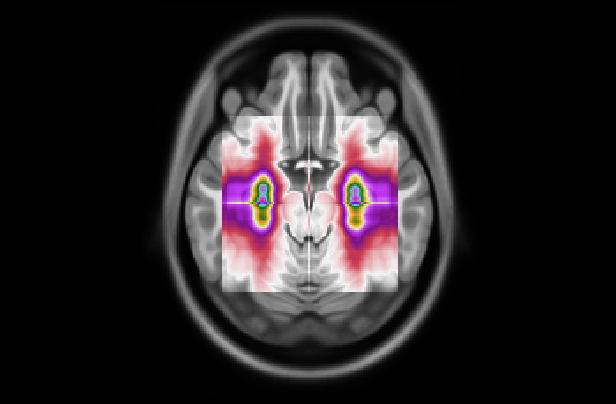

Refer to caption

Figure 7: (Left) Attention distribution for each plane averaged on all the five test to provide entire dataset distributions; (Right) Visualization of mean 3D attention map of entire dataset overlapped to MNI152 template

This section analyzes the interpretability of our approach and those proposed in (Wang et al., 2024; Altay et al., 2021). Our XAI method described in Section 4.3 allowed us to produce a 3D attentional map starting from the attentional weight distributions of the axial, coronal, and sagittal planes. The authors of AwareNet (Wang et al., 2024) designed the slice-aware module of this network to extract, as in our case, a distribution of attentional weights capable of summarizing the importance of each slice in the decision-making process. As a result, our approach can produce a 3D map also using the model proposed in (Wang et al., 2024).

Fig. 5 presents our diagnosis network’s average attentional weight distributions for each fold in the axial, coronal, and sagittal views. Upon examination of the histograms for each view, we observe a remarkable consistency in the distribution shapes across all five folds, indicating that our interpretability approach is stable despite the variation in the train/test set data. Specifically, the axial distributions reveal a consistent concentration of attentional weights around the initial slices. This trend suggests the model’s recurrent focus on the brain’s inferior regions, notably the areas where degenerative changes first manifest in AD, such as the hippocampus. In the coronal view, attentional weights are notably centered, indicating that the model consistently identifies the central part of the brain as significant. This central focus might correspond to the medial temporal lobe, including the hippocampus and the surrounding regions, further substantiating the axial findings. The sagittal view is the only bimodal distribution, suggesting that the model pinpointed symmetrical areas along this plane. We hypothesize that the network was focusing on the hippocampus since it adheres to all the constraints: situated in the inferior part of the brain, centrally located, and symmetrical. The consistency and specificity of these findings across multiple data folds strengthen the argument that our network could reliably identify specific brain regions as a critical biomarker for distinguishing between AD and CN subjects.